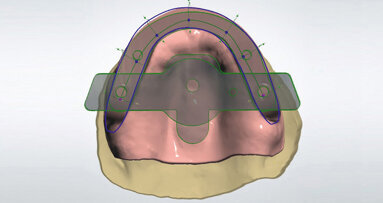

Obr. 1: CAD/CAM chirurgické šablony zcela omezují sklon vrtáku a hloubku preparace a jsou navrženy na základě dat týkajících se konkrétního pacienta z CBCT skenu a z intraorální kamery zpracovaných softwarem pro plánování implantátů

Obr. 2: Zkombinování CBCT a dat z intraorálních skenů usnadňuje podrobné, přesné předoperační plánování